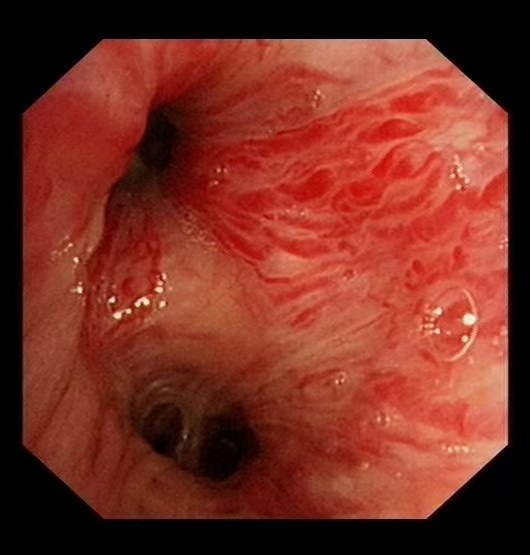

近日,重庆医科大学附属璧山医院(重庆市璧山人民医院)呼吸与危重症医学科成功救治一例罕见支气管淀粉样变合并大咯血患者。凭借血管介入技术、精准病理诊断及个体化治疗方案,患者术后咯血症状完全消失,目前已康复出院。这一病例的成功救治,彰显了我院在呼吸系统疑难重症领域的综合实力。